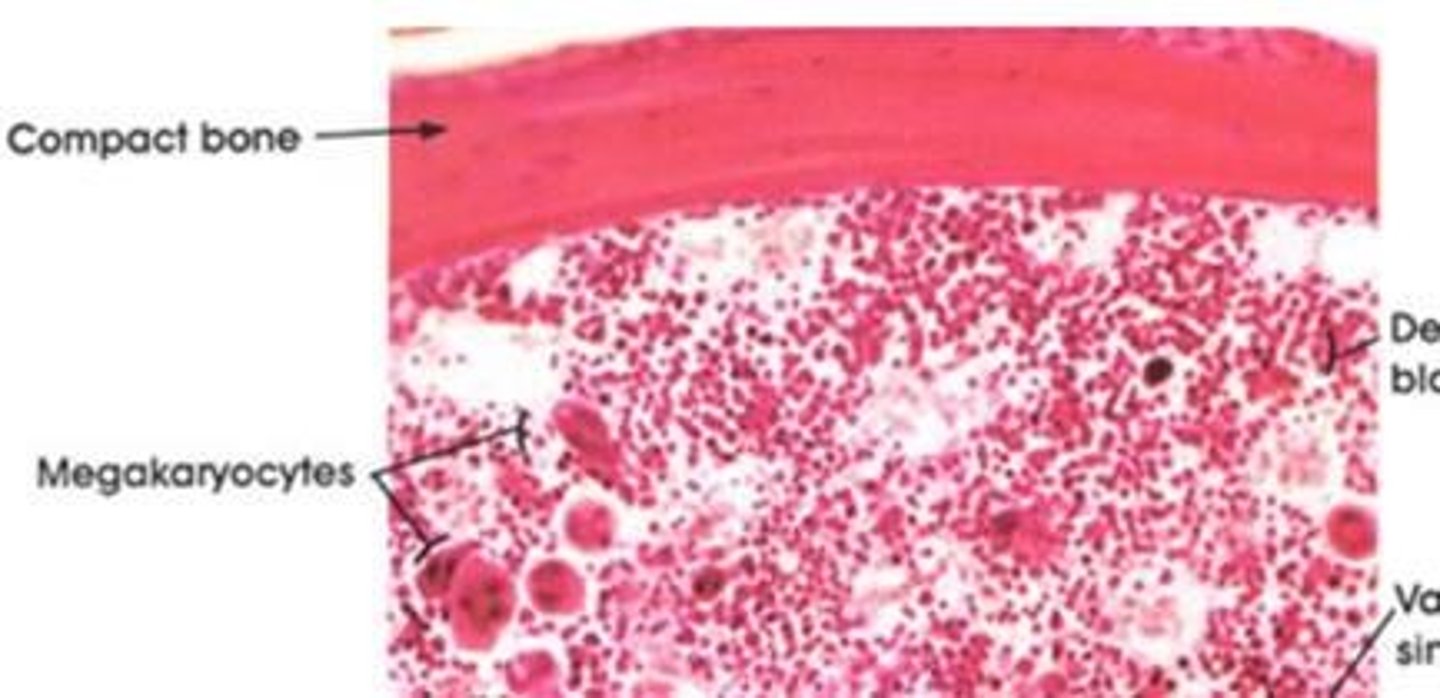

Hematopoiesis

whole blood formation (RBCs, WBCs and platelets)

All blood cells are made where? Are they made in the same place for adults and fetus?

adult: red bone marrow

Fetus: liver, spleen, and thymus

Where is red bone marrow located?

in the spongy bone of flat bones (skull, ribs, sternum, pelvis) and the proximal epiphyses of long bones

What is a megakaryocyte?

a large bone marrow cell responsible for the production of blood thrombocytes (platelets)